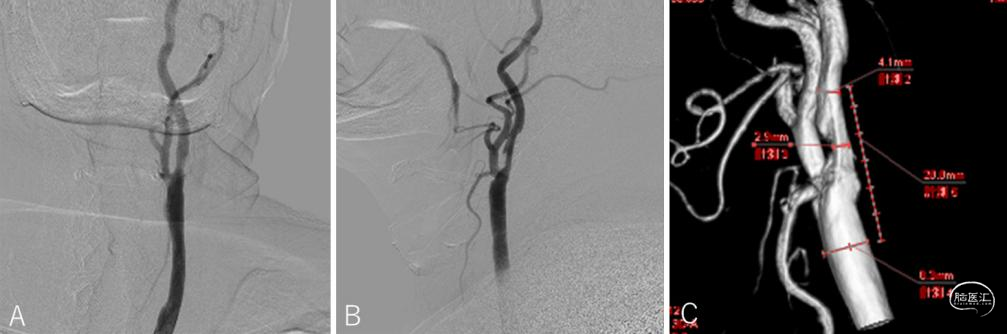

● 标准数字减影血管造影(DSA)显示与磁共振成像(MRI)相似的结果(图2),同样未能揭示病因。鉴于症状由特定头位诱发,提示血管动态受压可能,对其进行了头位变换的DSA检查(手术团队称其为“动态DSA”)。

图2:术前标准DSA检查